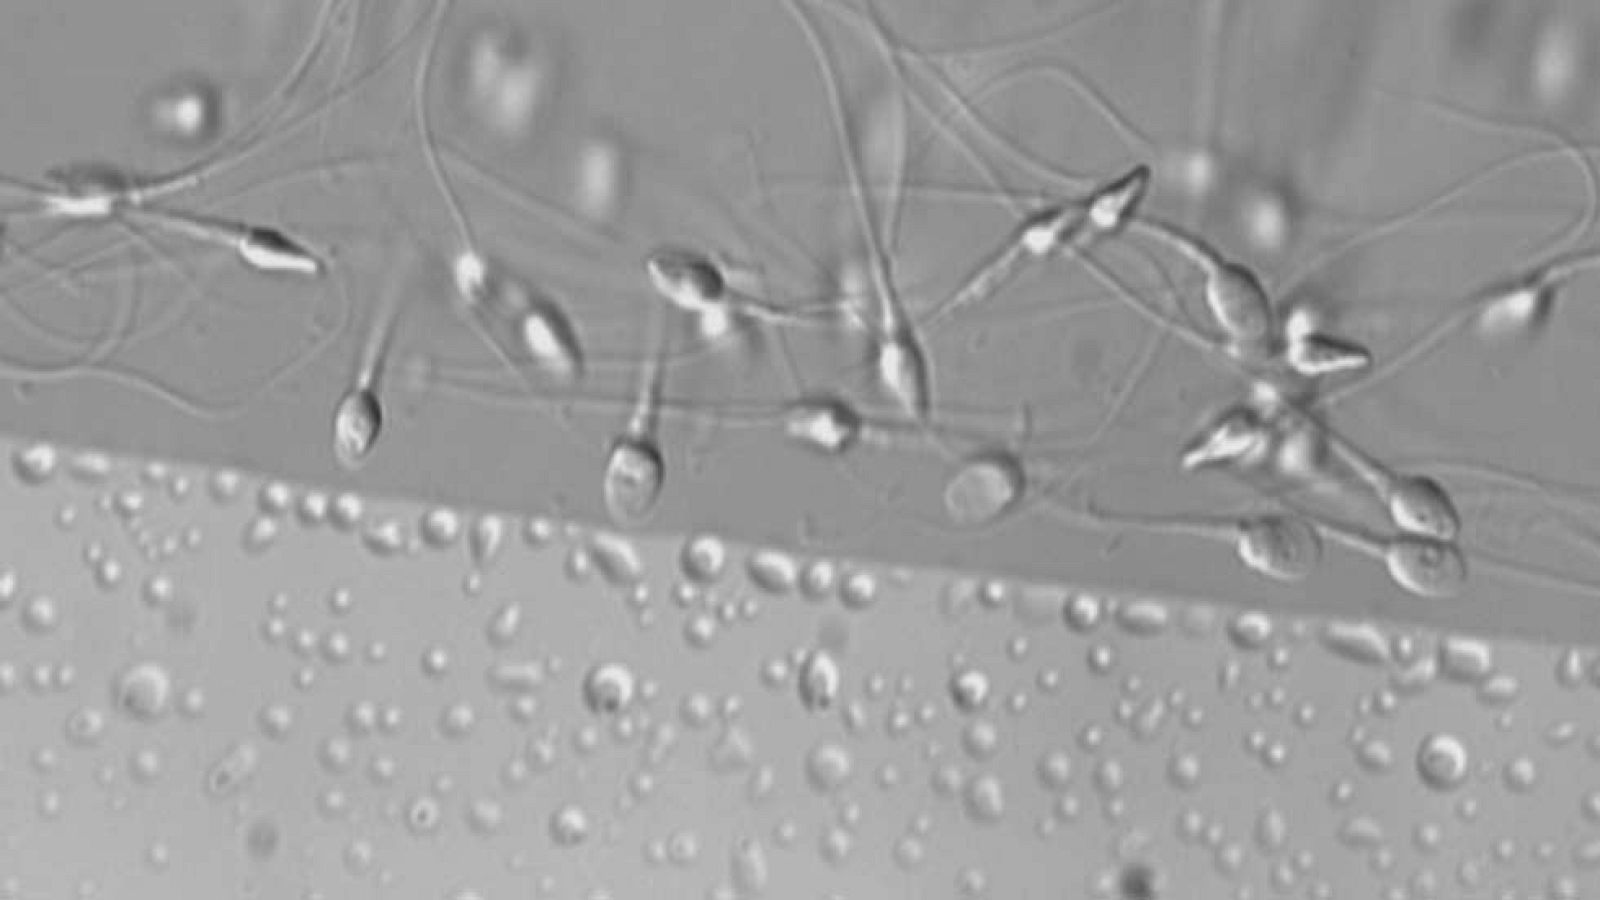

Aproximadamente tres de cada diez hombres en edad fértil tiene semen de mala calidad, inferior a los estándares marcados por la OMS. Son datos que se han presentado en un congreso sobre reproducción asistida que se celebra en Madrid. Factores ambientales, el estrés o una mala alimentación están detrás en la mayoría de los casos.